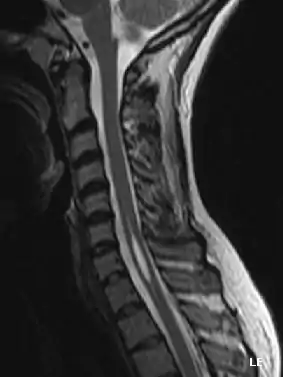

La siringomielia es un trastorno en el cual se forma un quiste dentro de la médula espinal. Este quiste se conoce como siringe o syrinx. Con el tiempo, el syrinx se expande y alarga, destruyendo el centro de la médula espinal. Puesto que la médula espinal conecta el cerebro con los nervios de las extremidades, este daño causa dolores, debilidad y rigidez en la espalda, los hombros, los brazos o las piernas. Otros síntomas pueden incluir dolores de cabeza (cefalea) y pérdida de la capacidad de sentir calor o frío extremos, especialmente en las manos. Cada paciente tiene una combinación distinta de síntomas.

Una serie de lesiones pueden obstruir el flujo normal del líquido cefalorraquídeo y redirigirlo hacia la médula espinal. Esto da lugar a la formación del syrinx o siringe, el cual se llena de líquido cefalorraquídeo. Las diferencias de presión a lo largo de la médula espinal hacen que el líquido se mueva dentro del quiste. Se cree que este movimiento continuo del líquido da lugar al crecimiento del quiste y causa daños adicionales a la médula espinal.